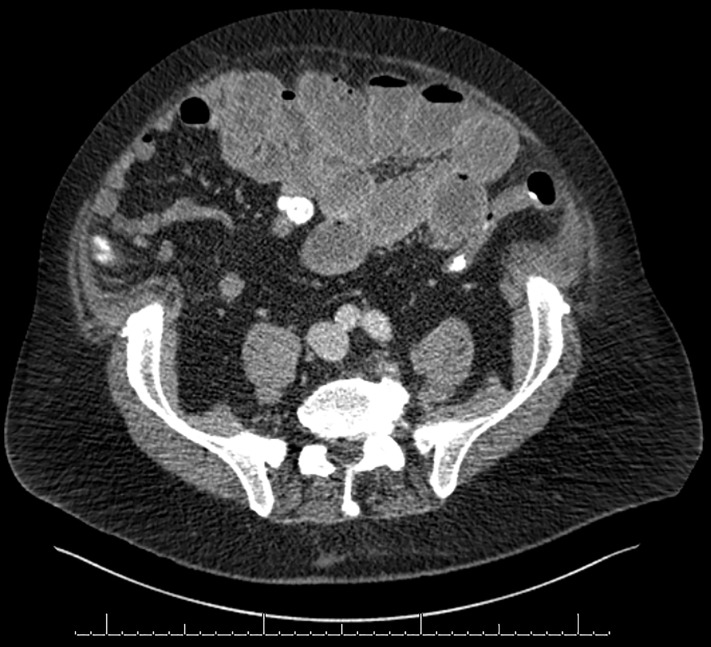

Αξονική τομογραφία. Ύποπτη στροφή μεσεντερίου άνω κοιλίας, εντερικός βρόχος στο κάτω δεξί τεταρτημόριο, διαχωρισμός στη μέση γραμμή κοιλίας (Ευγενική παραχώρηση Dr. V. Penopoulos)